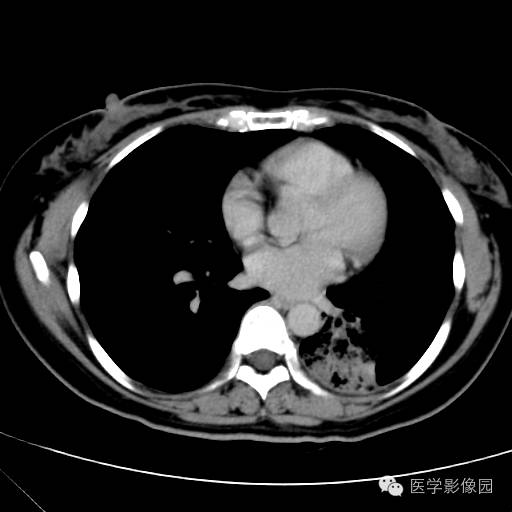

肺叶实变性支气管肺泡癌1例CT影像表现